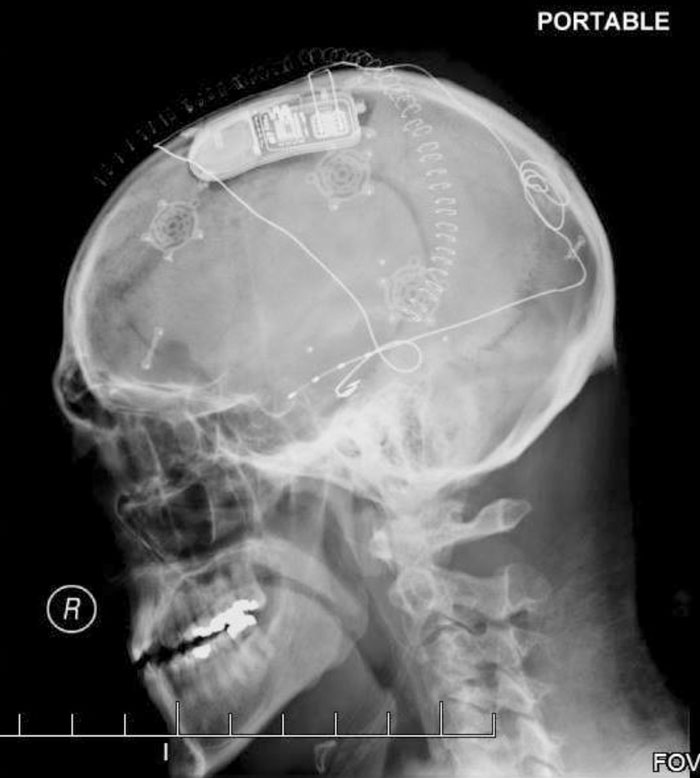

A Nice Clear X-Ray Showing My RNS Device, The Leads That Run To The Point Where My Seizures Originate

And also the brackets holding my skull together after my craniotomy (and the staples holding my scalp together).